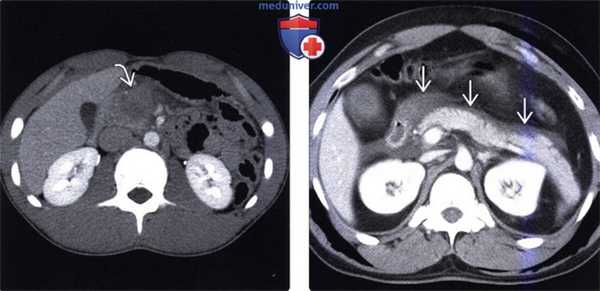

(Слева) На аксиальной КТ с контрастным усилением определяется нечетко различимый разрыв поджелудочной железы с наличием жидкости в сальниковой сумке, а также в забрюшинном пространстве.

(Справа) На аксиальной КТ с контрастным усилением у этого же пациента визуализируется жидкость (панкреатический сок) позади поджелудочной железы, распространяющаяся вдоль селезеночной вены. Практически во всех случаях также присутствуют вторичные признаки травмы, такие как жидкость около поджелудочной железы, гематома и инфильтрация жировой ткани, позволяющие сделать правильное заключение. (Слева) На аксиальной КТ с контрастным усилением определяется разрыв поджелудочной железы на уровне шейки. Целостность панкреатического протока нарушена. Была выполнена операция, удалены хвост и тело поджелудочной железы.

(Справа) На аксиальной КТ с контрастным усилением, выполненной 48 часов спустя от момента получения травмы, определяется разрыв поджелудочной железы и псевдокиста в сальниковой сумке. Скопление жидкости обусловлено утечкой жидкостного содержимого из разорванного панкреатического протока.